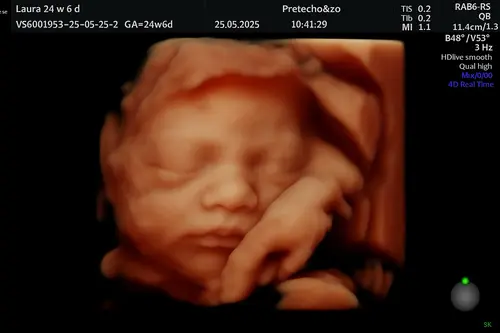

Ons menneke met 24 weken 💙

Wat een prachtig snoetje 😍